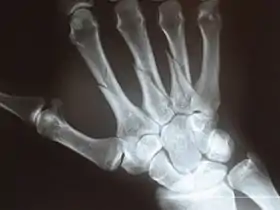

![]() عظيمات الرسغ الثمانية ومشط اليد كما تبدو بالأشعة السينية. عظيمات الرسغ الثمانية ومشط اليد كما تبدو بالأشعة السينية. | |